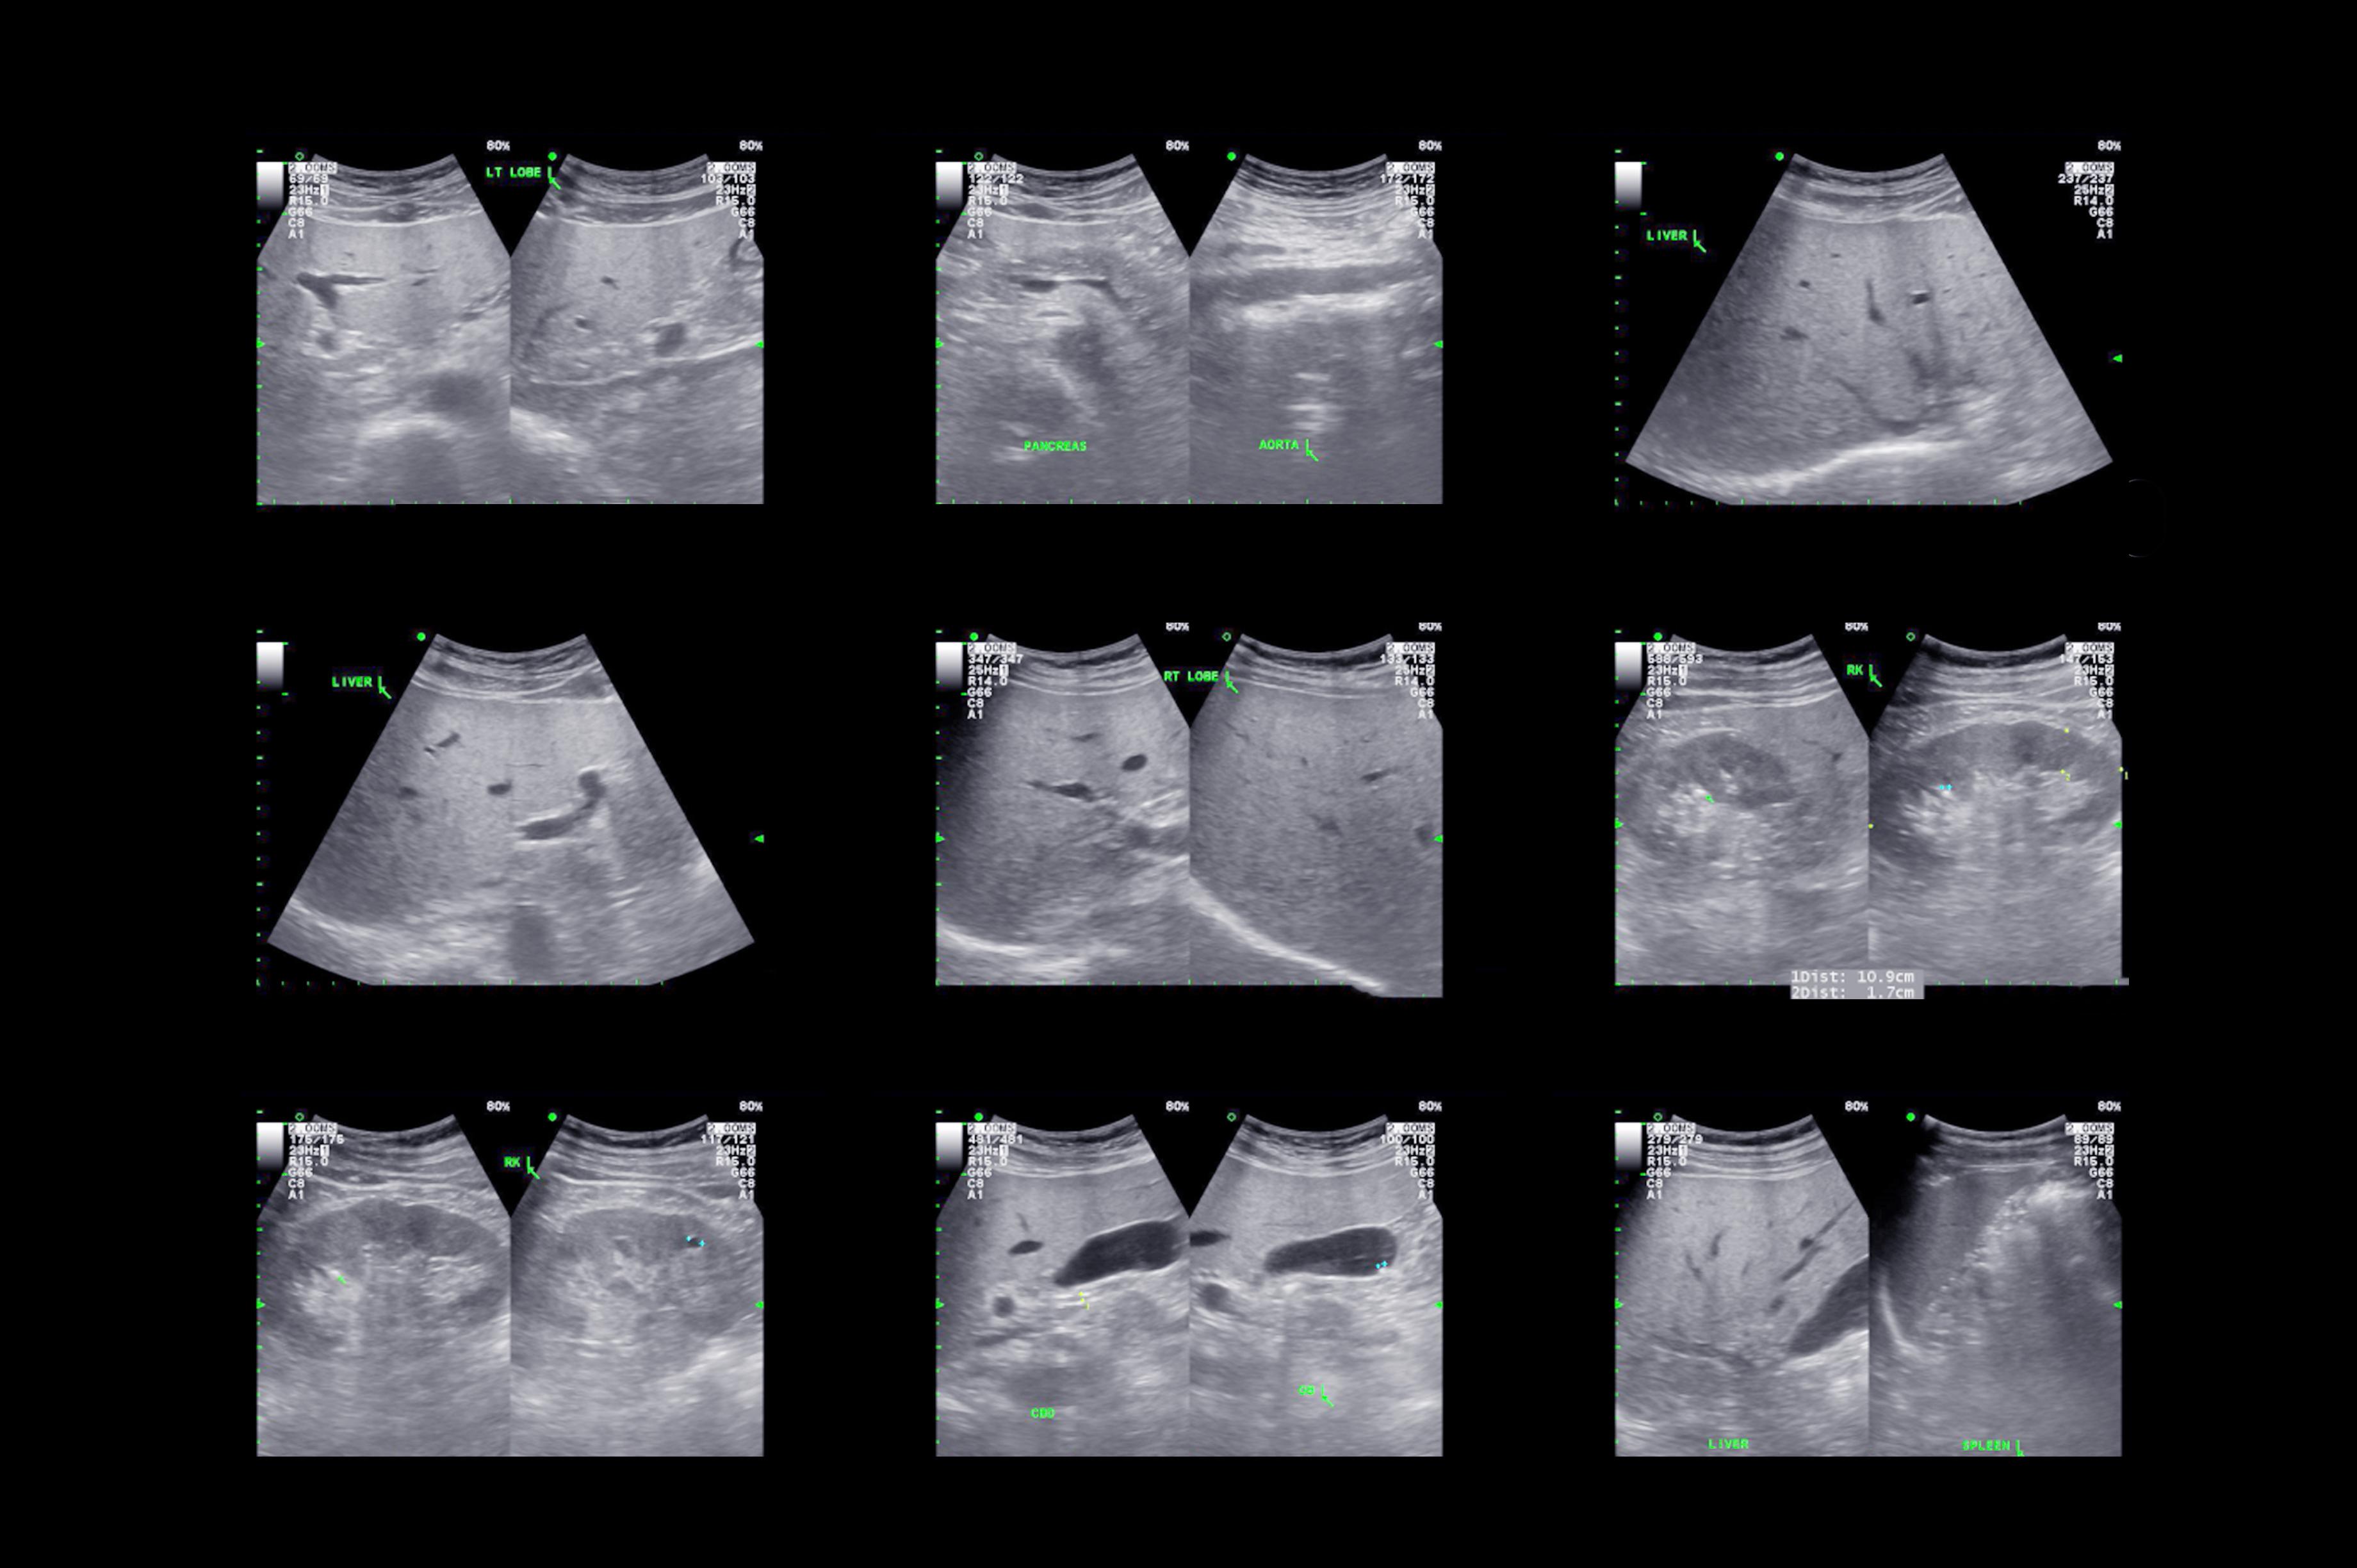

Réalisée au lit du malade, cette méthode diagnostique non invasive et non irradiante est utilisée comme un complément à l’évaluation des patients et des patientes. Elle intègre une multitude de données cliniques et des explorations échographiques ciblées : cardiaques (ex. : épanchement péricardique), pulmonaires (ex. : épanchement pleural, pneumothorax), urinaires (ex. : dilatation des voies urinaires), abdominales (ex. : hémorragie péritonéale, anévrisme de l’aorte), etc. L’ultrasonographie ciblée permet également de contrôler des procédures semi-invasives (ex : ponctions liquidiennes et vasculaires écho-guidées). « Sorte de stéthoscope amélioré, le POCUS aide à répondre spécifiquement à des questions binaires qui découlent de notre raisonnement clinique. Il nous apporte une expertise technique rigoureuse, néanmoins limitée par rapport à l’approche radiologique, plus descriptive et avancée », explique le Dr Olivier Grosgurin, médecin adjoint agrégé au Service de médecine interne générale et au Service des urgences.